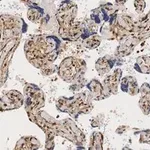

Monoclonal Anti-α-Tubulin antibody produced in mouse

clone DM1A, ascites fluid

Monoclonal Anti-α-Tubulin (mouse IgG1 isotype) is derived from the DM1A hybridoma produced by the fusion of mouse myeloma cells and splenocytes from immunized BALB/c mice. Purified chick brain microtubules were used as immunogen. The isotype is determined by a double diffusion immunoassay using Mouse Monoclonal Antibody Isotyping Reagents, Product Number ISO2. The product is Protein A purified Monoclonal Anti-α-Tubulin antibody conjugated to fluorescein isothiocyanate, isomer I. It is purified by gel filtration and contains no detectable free FITC. Anti-α-Tubulin FITC antibody, Mouse monoclonal specifically recognizes an epitope in the carboxy terminal part of α-tubulin. It localizes α-tubulin in human, monkey, bovine, chicken, goat, murine, rat, gerbil, hamster, rat kangaroo, amphibia, sea urchin, trypanosome, yeast, fungi and tobacco.